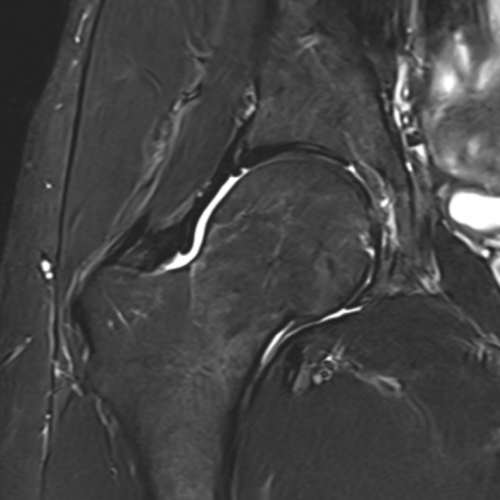

Cet examen est réalisé pour analyser les différentes structures anatomiques de la hanche : cartilage, labrum cotyloïdien, cotyle, tête fémorale, tendons fessiers (lame latérale du glutéal), tendon psoas, tendon ischio jambier

Cette examen permets de diagnostiquer:

- l‘arthrose (coxarthose)

- les conflits fémoro-acétabulaires

- les ostéonécroses de la tête fémorale

- les tendinobursites de la lame latérale du moyen glutéal

- les bursites péritrochantériennes

- une synovite ou un épanchement articulaire

- les fractures

- les tumeurs

- les lésions du labrum